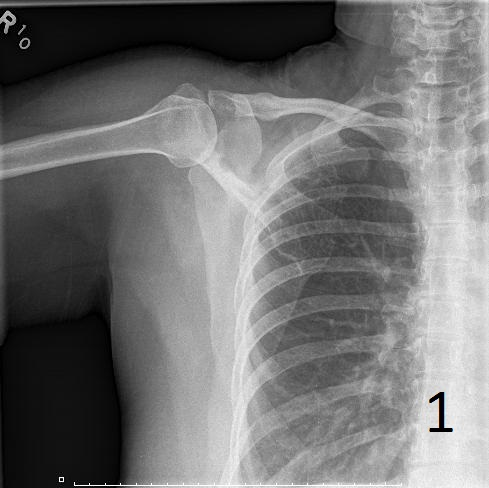

• Lesions are metaphyseal and diaphyseal (Fig. 1)

• Lytic lesion, with a “ground glass” appearance; trabeculae appear smudged as though somebody took a pencil eraser and smudged them

• Affected bone may present with a well defined sclerotic, expanded and thick reactive bone called rind of sclerosis

Fig. 1. AP plain x-ray of fibrous dysplasia of the right shoulder showing an expanded lytic lesion involving the spine of the scapula.